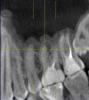

belbucha Опубликовано 29 января, 2011 Поделиться Опубликовано 29 января, 2011 Доброго времени суток всем.Несколько дней назад начали беспокоить очень сильные боли в области гайморовой пазухи и зубов с правой стороны. Сделал рентген снимок для ЛОРа, направили к нему с диагнозом гайморит.В больнице сделали прокол, увидели много гноя, сказали сделать КТ, дабы исключить вариант заболевания от зубов (одонтогенного генеза), т.к. не было у меня ни соплей, ни еще каких-либо симптомов, кроме боли.Сделали КТ, и выдали вот такое заключение: "В правой верхнечелюстной пазухе визуализируется мягкотканное содержание с пузырьками воздуха в своем составе, занимающее 2/3 всей полости, одонтогенного генеза (16 зуб радикулярная киста медиального щечного корня проросла в правую в/ч пазуху, разрушив костное дно). В левой в/ч пазухе определяется утолщение слизистой нижней стенки до 7-9мм одонтогенного генеза, причиной была радикулярная киста медиального щечного корня 26 зуба. Передние и средние ячейки решетчатого лабиринта справа, заполнены мягкотканным содержимым, слизистая гипертрофирована. Основной (клиновидный) синус - незначительное утолщение нижней стенки. Заключение: КТ картина соответствует правостороннему гнойному одонтогенному гаймориту. Этмоидиту. Радикулярная киста 16,15,26 зубов." На руках у меня только заключение и диск с КТ, снимков нет. У меня нет медицинского образования, но насколько я смог увидеть хоть что-то, выкладываю скриншоты КТ.При необходимости, могу выложить на какой-нибудь обменник весь диск, ISO-образ его. Скажите люди добрые, что меня ждет? что можно предпринять в таком случае? Очень не хочется остаться без жевательных зубов в 25 лет. Период сейчас крайне сложный, супруга на 9-ом месяце, ей нужна моя помощь и поддержка, некогда мне по болницам лежать.Заранее всем спасибо. Ссылка на комментарий

Scrabble Опубликовано 29 января, 2011 Поделиться Опубликовано 29 января, 2011 С 16 неоднозначно-может быть, и удалить придётся, 26-27 перелечите у эндодонтиста. 15 корень удаляется, похоже. Ссылка на комментарий

Bier Опубликовано 29 января, 2011 Поделиться Опубликовано 29 января, 2011 надо еще прицельные снимки сделать. Если возможно перелечить - перелечивайте, если нет - удаляйте. Потом имплантаты поставите. Ссылка на комментарий